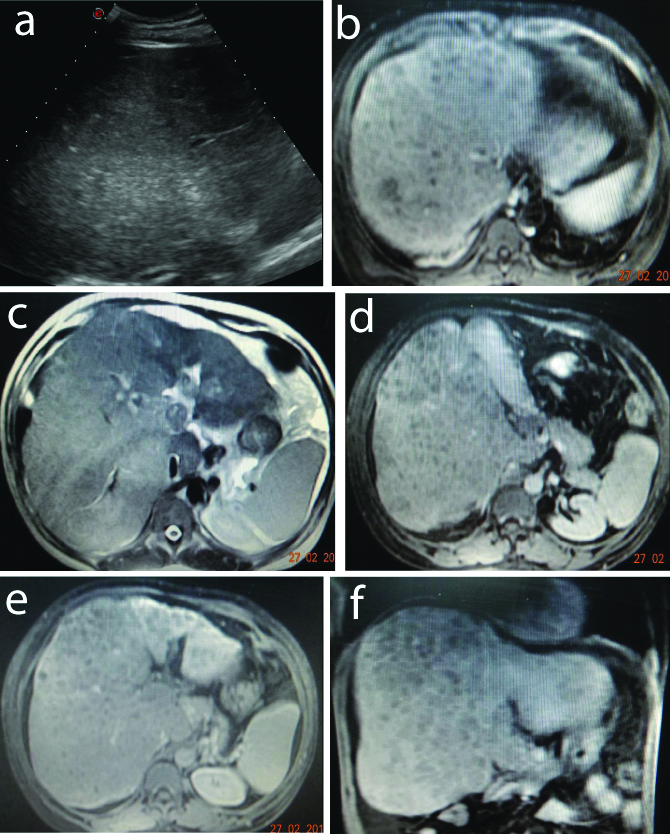

Nutmeg Liver Appearance Ultrasound . Limited enhancement was seen of the hepatic veins. The macroscopic examination reveals a liver with. Gross pathology demonstrating a nutmeg liver. The findings were consistent with congestive hepatopathy and described as a nutmeg liver. Computed tomography scan showed a nutmeg liver suspected for increased venous pressure by thrombosis of the liver. Nutmeg liver refers to the mottled appearance of the liver as a result of hepatic venous congestion. A ct scan of the abdomen and pelvis displayed a diffusely heterogeneous appearance with a mottled attenuation most pronounced in the sub capsular region of the liver. This fibrosis pattern observed in hepatic congestion is known as “inverse lobulation”. A nutmeg liver appearance is due to a perfusion abnormality of the liver usually as result of hepatic venous congestion. Radiologically, it is most appreciable on.

Nutmeg liver refers to the mottled appearance of the liver as a result of hepatic venous congestion. Gross pathology demonstrating a nutmeg liver. A ct scan of the abdomen and pelvis displayed a diffusely heterogeneous appearance with a mottled attenuation most pronounced in the sub capsular region of the liver. This fibrosis pattern observed in hepatic congestion is known as “inverse lobulation”. Limited enhancement was seen of the hepatic veins. Radiologically, it is most appreciable on. Computed tomography scan showed a nutmeg liver suspected for increased venous pressure by thrombosis of the liver. The findings were consistent with congestive hepatopathy and described as a nutmeg liver. The macroscopic examination reveals a liver with. A nutmeg liver appearance is due to a perfusion abnormality of the liver usually as result of hepatic venous congestion.